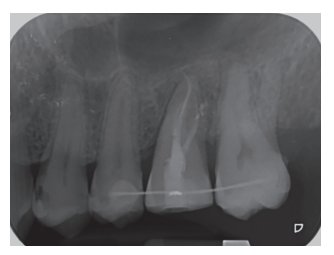

Caso clínico: se presenta el caso de un varón de 28 años, que acudió a consulta por la presencia de unos restos radiculares en localización de primer molar superior izquierdo. Se realizó un autotrasplante dental, siendo el diente donante el tercer molar superior izquierdo, que se trasplantó al alveolo del primer molar, mostrando buena evolución clínica y radiográfi ca.

Clinical case: a clinical case of a 28-yearold man is presented, who went to dental clinic for removal of left fi rst molar roots. An autotransplant was performed using left third molar as donor tooth, which was transplanted into fi rst molar alveolus, showing promising clinical and radiographic evolution.

Por tanto, debido a las altas tasas de éxito descritas en la literatura, el objetivo del presente caso clínico es evaluar clínica y radiográficamente la realización de un autotrasplante con el ápice cerrado, para reponer un primer molar superior izquierdo, como alternativa terapéutica a la colocación de un implante en un paciente adulto.